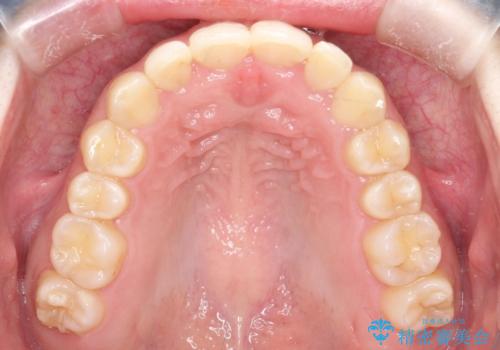

インビザラインでの前歯のガタガタの矯正

- 上下の前歯のがたつきを主訴に来院されました。

歯と歯の間をわずかに削りスペースを作り、インビザラインにて矯正治療を行うこととしました。

使用時間を守っていただけたので、スムーズに矯正を終了することができました。